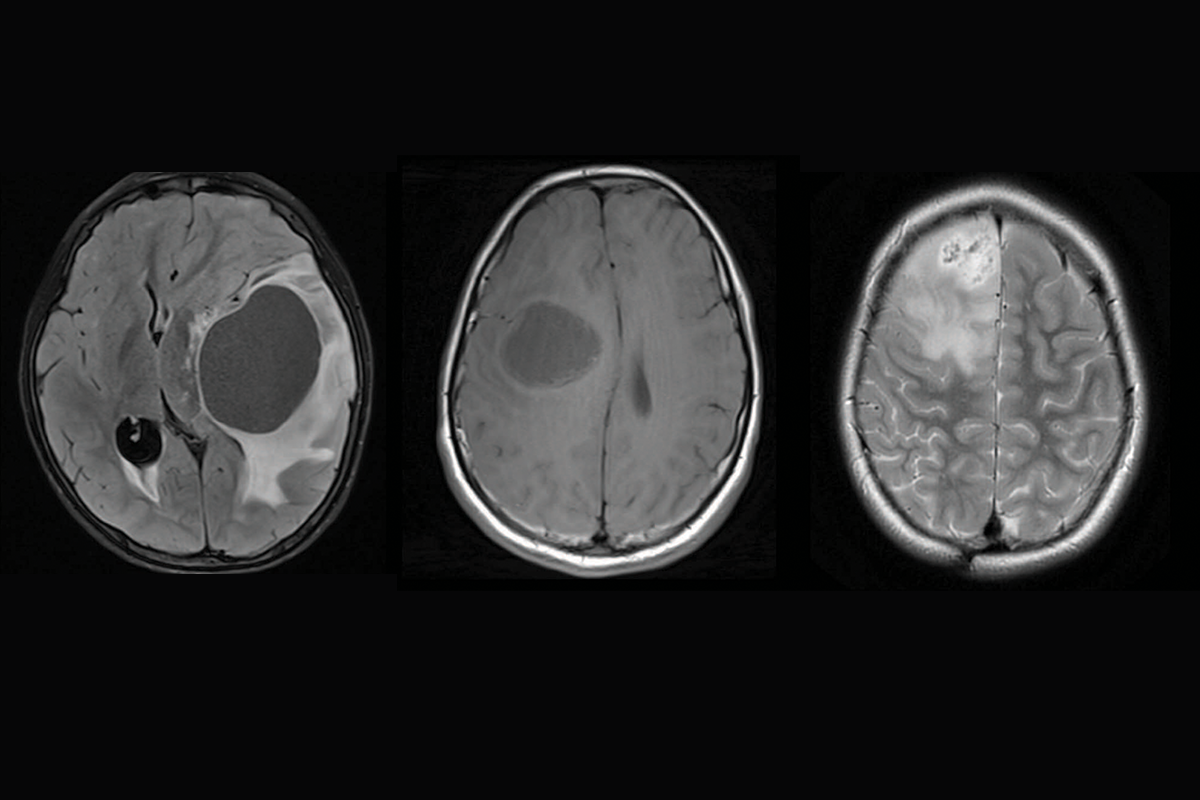

SickKids Cancer Sequencing Program

In 2016, SickKids established the world-leading SickKids Cancer Sequencing (KiCS) Program, which was designed to analyze the genetic make-up of a child’s cancer to determine a patient’s unique genetic fingerprint, identify the cause of the tumor, gain information about prognosis, and implement personalized treatments. Together with PROFYLE, a trailblazing pan-Canadian program being conducted in partnership with the Terry Fox Research Institute, multiple childhood cancer foundcations, and all 16 paediatric cancer programs across Canada, KiCS matches nationally-collected sequencing data with potentially life-saving drugs.